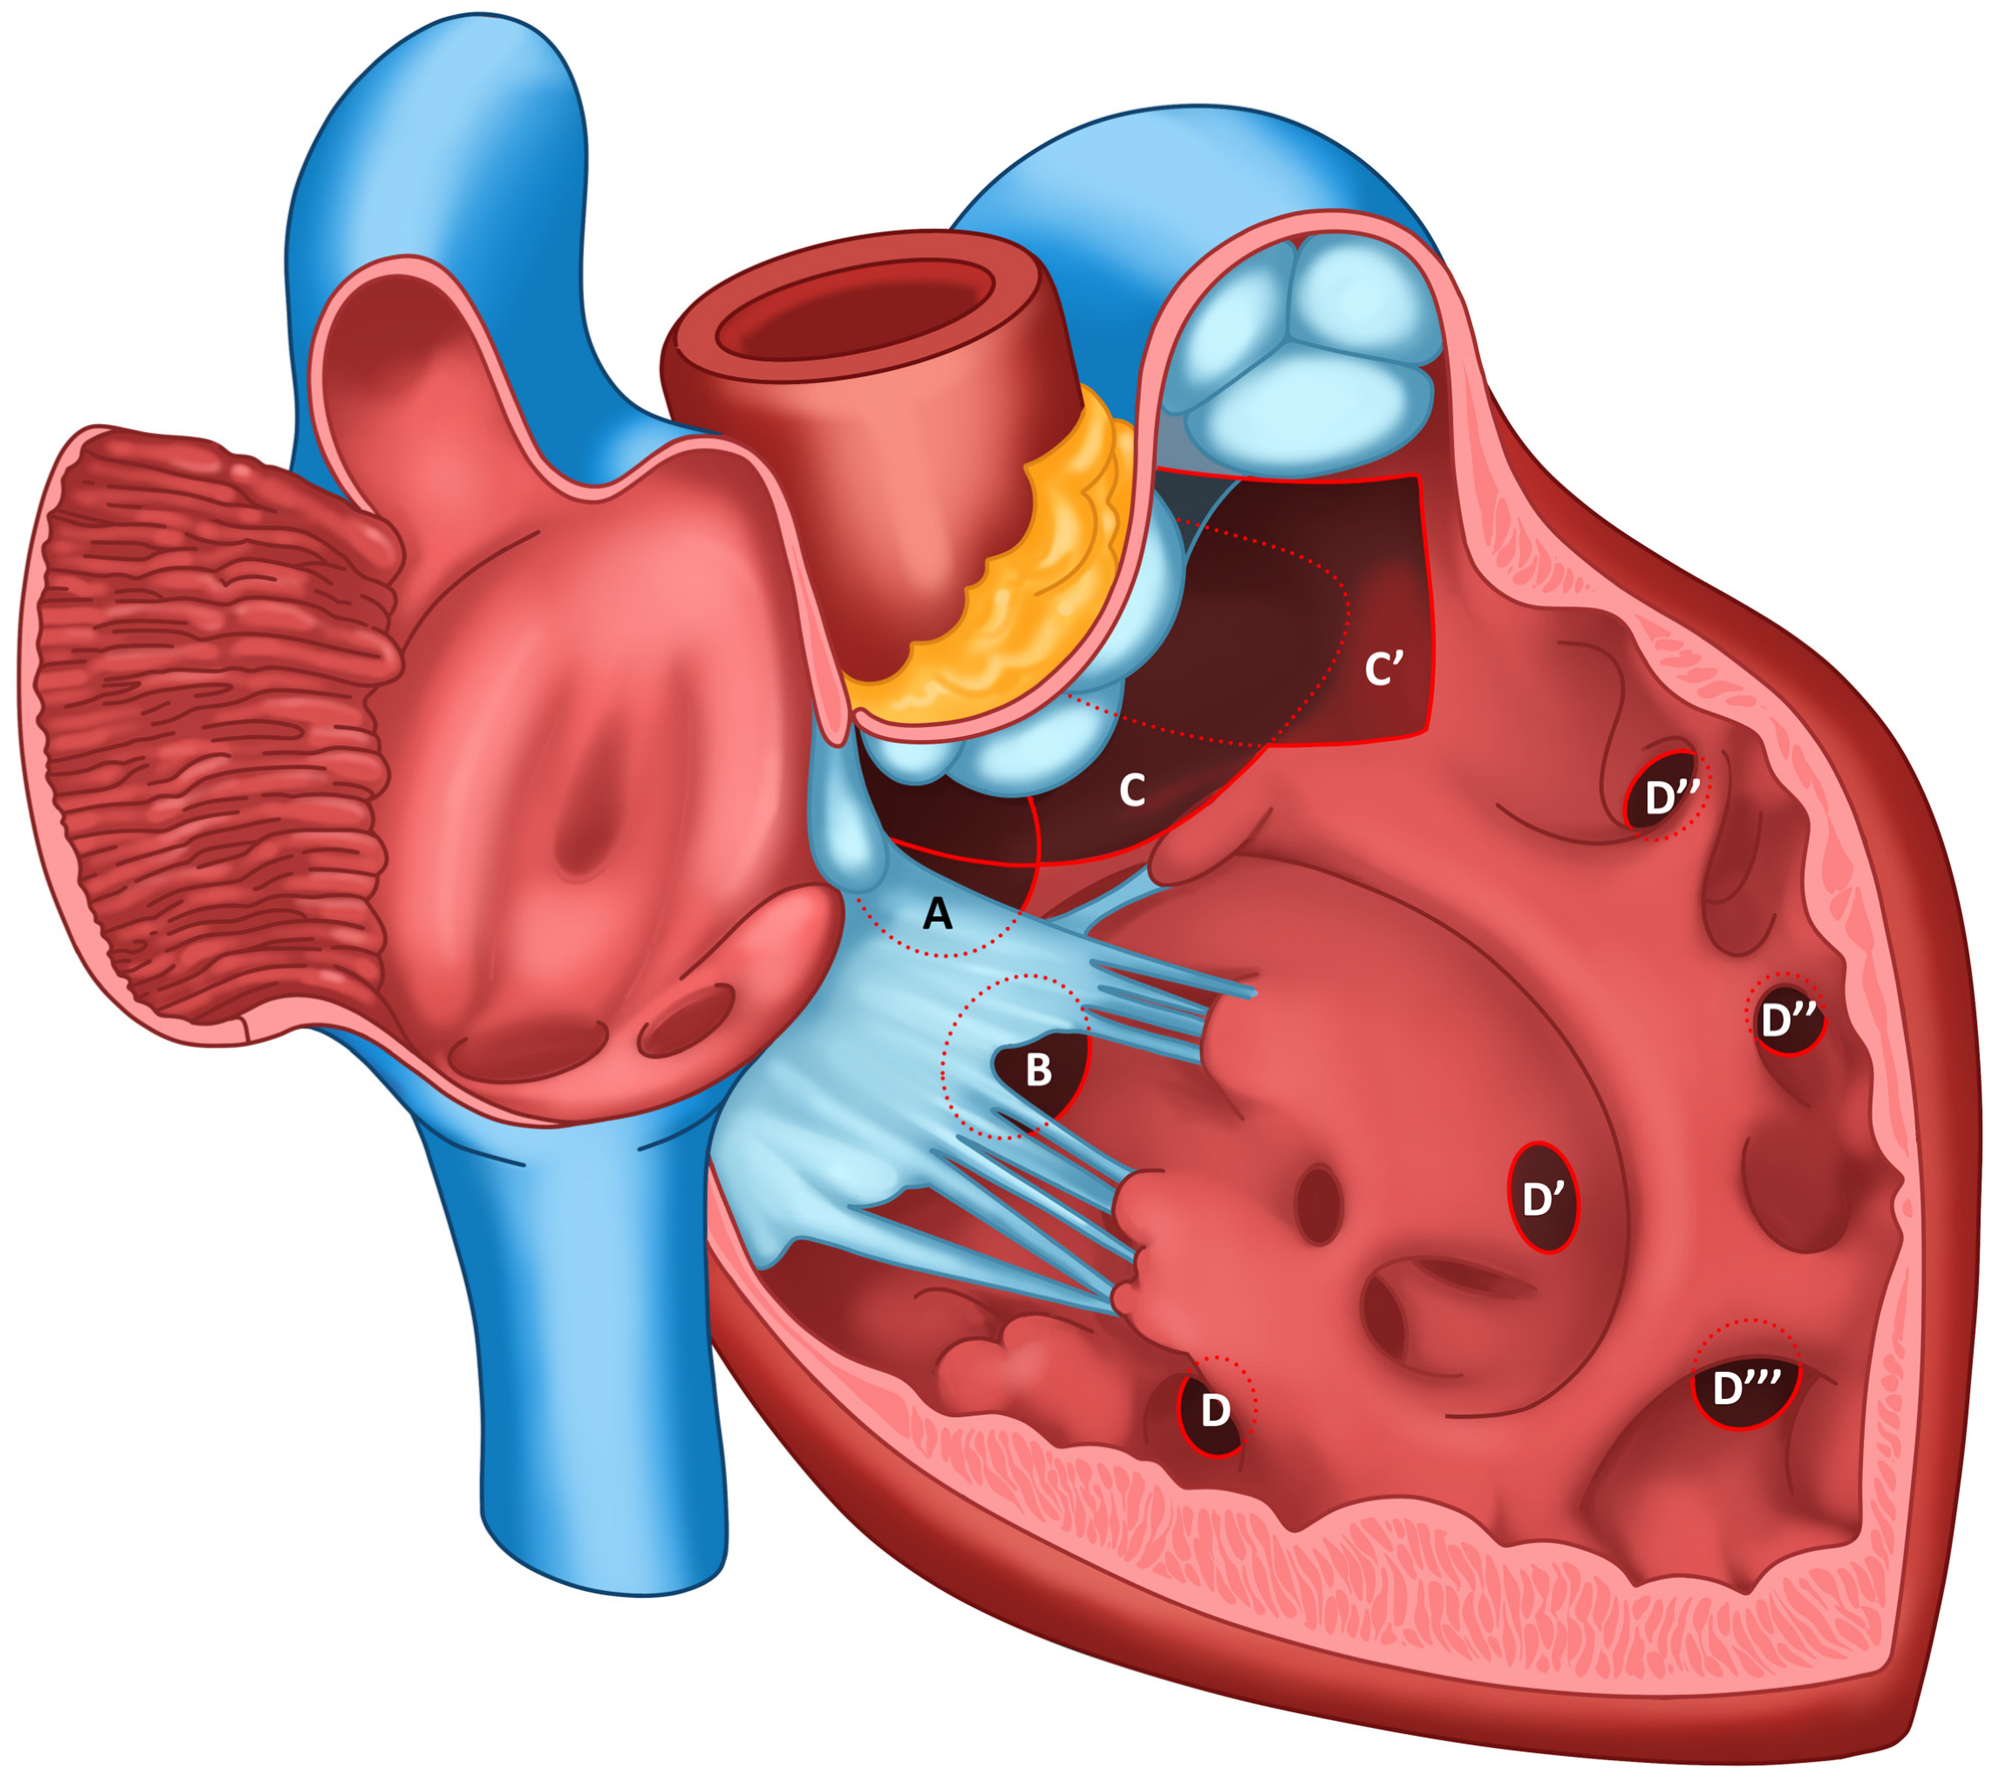

3. Nomenclature of Ventricular Septal Defects

1. Introduction